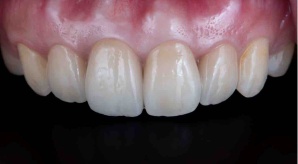

¥¤¥ó¥¹¥¿¥°¥é¥à¤ËºÜ¤»¤Æ¤¤¤ëÅö±¡¤Î¾ÉÎã¤Ç¤¹

ðÌî»õ²Ê¾ÉÎã¡¶ºÀµ¥¤¥ó¥×¥é¥ó¥È¥»¥é¥ß¥Ã¥¯